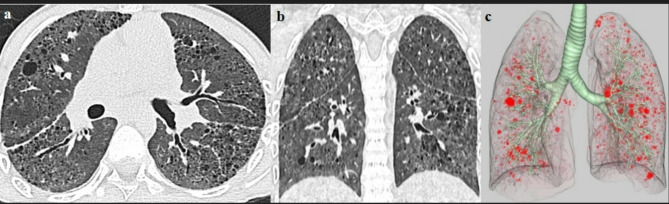

Case presentation: We present the case of a 15-year-old male from Senegal who recently arrived in Italy, presenting with severe respiratory distress and hypoxemia. The patient, born full-term, had a long history of chronic cough, recurrent respiratory distress, and poor growth since early infancy. Upon hospitalization, he tested positive for SARS-CoV-2 and exhibited signs of chronic respiratory failure and severe malnutrition. An extensive diagnostic work-up, including a chest CT scan, revealed small cystic-like air spaces and diffuse ground-glass opacities. Whole-exome sequencing confirmed the diagnosis of SP-C deficiency by identifying a heterozygous missense mutation (c.218t>C, Ile73Thr) in the third exon of the SFTPC gene. Treatment with steroids, azithromycin and hydroxychloroquine was initiated. Despite pharmacological treatments, the patient remained oxygen dependent due to the severity of this condition and required long-term bilevel non-invasive ventilatory support.